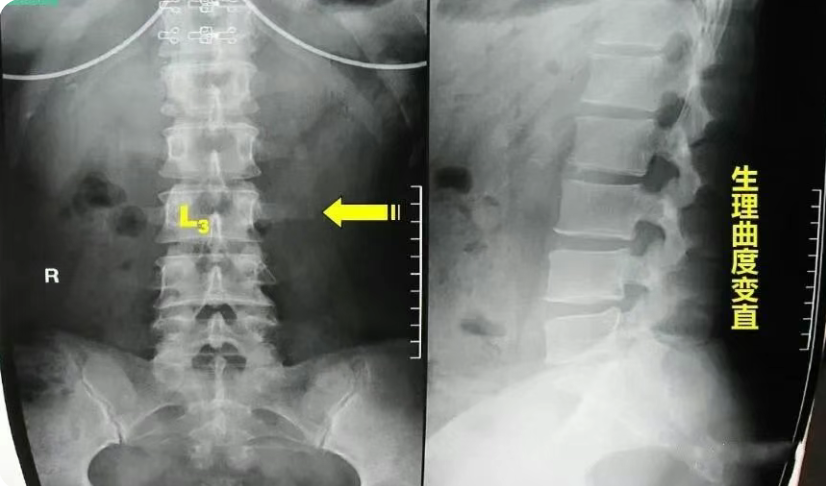

第三腰椎横突综合征是指腰三横突及周围软组织的急慢性损伤、劳损及感受风寒湿邪,致腰三横突发生无菌性炎症、粘连、变性及增厚等,刺激腰脊神经而引起腰臀部疼痛的综合症候群。

腰椎一共有五个,正常腰椎呈生理性前凸,第3腰椎位于前凸的顶部,腰椎在传导重力时,常是以第3腰椎为其活动中心,故成为腰椎前屈、后伸、左右旋转活动的枢纽。因此,两侧横突所受的牵拉应力最大。在生长发育过程中,受拉应力最大的横突其生长速度也最快。腰三横突位于肋弓与髂嵴之间,横突向后成30度角左右,向前倾斜15度左右,近尖部骨面增厚粗糙。

第三腰椎横突比其他腰椎的后伸曲度大,向侧方延伸最长,位于腰椎中部,两侧腰椎横突联线形成以第三腰椎横突尖为顶点的纵长菱形。第一、二腰椎横突外侧有下部肋骨覆盖,第四、五腰椎横突深居于髂骨内侧,只有第三腰椎横突缺乏肋骨及髂骨保护,因而易受损害。

第三腰椎位于腰前凸曲线之顶点,背阔肌的髂腰部分纤维止于第三腰椎横突,腰大肌的部分肌纤维也止于此处,骶棘肌的一部分肌纤维也止于此,因此,第三腰椎成了腰椎的活动中心,起到了类似接力站的作用,为腰椎屈、伸、侧弯及旋体的枢纽,所受的杠杆作用最大。而第三腰椎横突更是受力点。由于第三腰椎横突较长,以致附着于此处的肌肉、筋膜、韧带能有效地保持脊柱的稳定性及正常的活动。较长的横突又能增强肌肉的杠杆作用,肌肉收缩牵拉机会多,拉力最大,当这些组织异常收缩时,横突末端首当其冲。这种解剖特点构成末端易受损伤的基础,往往因劳损而引起横突末端周围的纤维织炎。横突越长,发病率越高,以单侧多见。